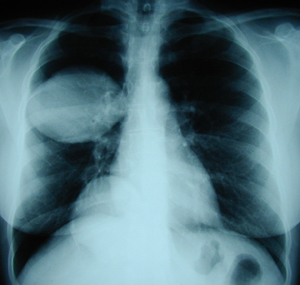

Εικόνα 1

Οπισθιοπροσθία ακτινογραφία του θώρακος. Διακρίνονται δύο μεγάλες κύστες εχινοκόκκου του δεξιού πνεύμονος, μια στον άνω και η άλλη στον κάτω λοβό.